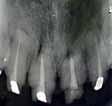

The Dental Panoramic Tomogram (DPT) confirmed the presence of all permanent teeth including the developing third molars (Figure 3). Root morphology appeared normal. The upper right central incisor had a root canal filling. The upper standard occlusal

radiograph revealed that the upper right central incisor had an adequate root filling with no periapical area. In the cephalometric assessment (Figure 4), the ANB value of 7° suggested a moderate Class II skeletal pattern. The vertical proportions were within normal values. The upper incisors were proclined at 122° and the lower incisors were of average inclination at 94°. The interincisal angle was reduced at 119°. The lower incisor to APo and the lower lip to E line were within normal limits.